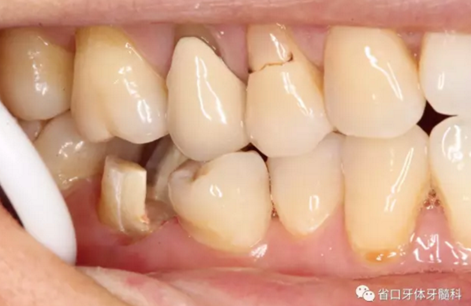

圖3 牙體預(yù)備后,近中頰側(cè)牙體缺損平齊齦緣;近頰根管口流動樹脂覆蓋牙膠不足,下次改進(jìn)